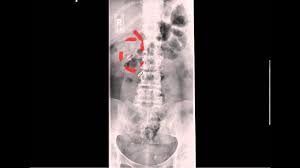

Kidney ureter and bladder ie kub. We then made a 1 cm incision on the needle and then dilated the tract with coaxial fascial dilators over the wire under fluoro up to 16 french and then used amplatz dilator to place a safety wire and dilate up to 18 french. Ct of abdominal organs kidney ureter and bladder without contrast.

We then made a 1 cm incision on the needle and then dilated the tract with coaxial fascial dilators over the wire under fluoro up to 16 french and then used amplatz dilator to place a safety wire and dilate up to 18 french. 30 partial or subtotal nephrectomy kidney or renal pelvis or partial ureterectomy ureter procedures coded 30 include but are not limited to. Cpt code procedure 76506 u s exam of head 76536u s soft tissue neck thyroid parathyroid etc 76604 u s chest 76641 u s breast uni or bi 76700 u s abdomen complete 76705 u s abdomen limited 76706 u s abdomen aorta aaa screening 76770 u s retro renal aorta nodes 76775 u s retro limited 76776 u s transplanted kidney. Knee 3 views.